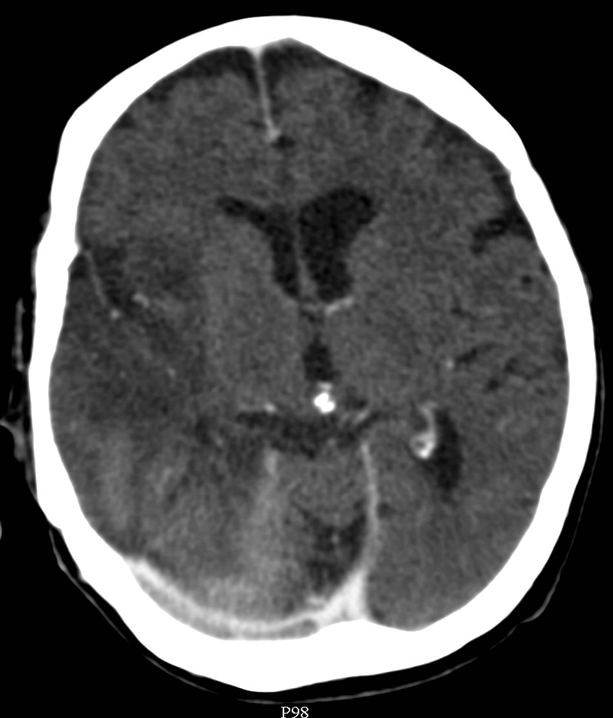

The key question whether the patient ha intracranial hematoma, which causes mass effect and later leads to vasoconstriction. In the presence of open skull fracture signed by liquorrhea severe infection and herniation might occur. To exclude intracranial hemorrhage CT is the modality of choice.

All three types of intracranial hematoma can occur as a result of head trauma:

• Rupture of the meningeal arteries may give rise to an epidural hematoma. At the site of the hematoma skull fracture can be observed.

4.Middle-aged man some days after direct head trauma. On noncontrast CT a lens-shaped, slightly inhomogenous epidural hematoma can be seen, that causes compression of the right lateral ventricle (left panel). In bone window skull fracture without dislocation can be found at the site of the hematoma (right panel).

• Subdural bleeding is caused by injured bridging veins (elongation, tears) e.g. when a sudden deceleration occurs. This type of injury generally is not associated with a fracture.

5. A middle aged chronic alcoholic male. On unenhanced CT a typical crescent shape subdural hemorrhage is seen on both sides. Because of its etiology it extends across suture lines.

• Subarachnoid hemorrhage develops after vascular injury or aneurysm rupture.

6. Middle aged female fell of a ladder. On the unenhanced CT scan the basal cisterns are filled corresponding to a subarachnoid hemorrhage.

• Contusion hemorrhage occurs upon sudden deceleration (e.g. car accident - collision) when the brain parenchyma due to its inertness keeps moving and hits the cranial bone. Frequently, contusion develops on the opposite side as well, since on an abrupt stop the brain collides with the bone than bounces off and hits the opposite wall of the skull. (coup - contrecoup effect)

7. Elderly female was suffered a direct hit in the parietal region. Coronal reconstruction of a unenhanced CT scan: At the site of the impact on the right side parietally a typical lens shaped epidural hematome is formed. On the opposite side in the temporal lobe at the contrecoup contusion site parenchymal bleeding is seen